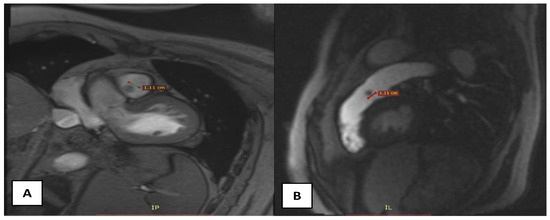

A 58-year-old male patient with multiple cardiovascular risk factors (high blood pressure, dyslipidemia, peripheral arterial disease, smoker) and a relevant family history (father had a myocardial infarction at age 56) with a history of pituitary adenoma surgery presented with persistent exertional dyspnea. TTE revealed a round, oval tumor attached to the pulmonary valve. The ejection fraction was estimated visually at 55%, with no segmental or global kinetic abnormalities and no signs of pulmonary thromboembolism (PE). The dyspnea persisted; therefore, the patient underwent coronary angiography, which revealed chronic occlusion of the circumflex artery, severe distal stenosis of the right coronary artery, and severe stenosis of the intermediate branch (Figure 1A,B). To accurately assess the tumor formation, the patient underwent cardiac MRI, which described a tumor formation (1.1 × 0.8 cm) as iso-/hypointense on T1-weighted sequences, mildly hyperintense on T2-weighted sequences, with no central enhancement but peripheral enhancement with gadolinium on delayed post-contrast sequences. These tissue characteristics supported the diagnosis of a papillary fibroelastoma (Figure 2A,B). Additionally, no other cardiac tumor structures were identified, and no signs of acute or chronic pulmonary embolism were detected. After obtaining the patient’s written consent and following discussions within the Heart Team, the patient underwent excision of the tumor formation from the pulmonary valve and coronary artery bypass grafting. Intraoperative transesophageal echocardiography (TEE) revealed a round, oval, mobile, well-defined tumor approximately 1.1 × 0.8 cm in diameter, attached to the surface of the right cusp of the pulmonary valve (Figure 1C,D). The tumor did not exert a hemodynamic impact on the valve, was not associated with pulmonary stenosis, and was accompanied by only mild pulmonary regurgitation. No other significant valvular pathologies were observed, and there was no echocardiographic evidence of PE. The surgical intervention was performed via sternotomy, under cardiopulmonary bypass with central cannulation: arterial in the ascending aorta and venous in the right atrium. Cardiac arrest was achieved using Calafiore cardioplegia. Initially, the distal coronary anastomoses were completed, followed by a longitudinal incision of approximately 4 cm in the pulmonary trunk to access the tumor. The tumor was friable, mobile, measuring approximately 1.1 × 1.0 cm, and attached to the pulmonary artery side of the right cusp of the pulmonary valve (Figure 3A). It was completely resected along with a small portion of the right pulmonary cusp that included its implantation base. Since only a small amount of valvular tissue was resected, valve repair was successfully performed using a continuous suture with 5.0 Prolene, Ethicon Inc., Cornelia, GE, USA, without the need for autologous pericardium or other biological materials (Figure 3B–D). Subsequently, the proximal coronary anastomoses were completed. No residual pulmonary regurgitation was detected. No other tumor formations were detected intraoperatively. The macroscopic appearance of the tumor was similar to a sea anemone when placed in serum (Figure 4A). The diagnosis of papillary fibroelastoma was confirmed by histopathological analysis (Figure 4B,C). The postoperative course was favorable and without complications, and the patient was discharged without further complaints of dyspnea.

Figure 2. (A)—transversal section on IRM demonstrating a 1.1 × 0.8 cm spherical structure attached to the pulmonary valve; (B)—sagittal section on IRM.